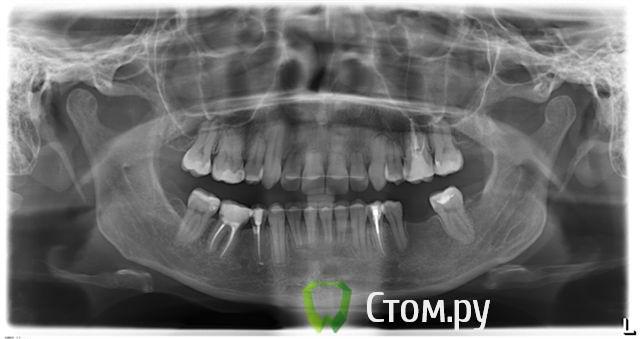

Александрстрад Опубликовано 8 ноября, 2011 Поделиться Опубликовано 8 ноября, 2011 Уважаемые доктора! Потерял и веру и надежду в возможность решения проблемы у своей жены. Одел на нее брекеты у знакомых ортодонтов в Москве, результаты, которых видел. В процессе лечения консультировался и ЦНИИСЕ у Арсениной и у других докторов, работал в крупнейшей медицинской компании, доступ к врачебной базе был очень большой. В процессе лечения все говорили что лечение идет нормально, а когда сняли брекеты ужаснулись все. Хронология лечения у ортодонта описана ниже, включая проблемы, которые мы получили после лечения.1. Показания к лечению брекет-системамиХруст при жевании в правом суставе.Замещение отсутствующего на нижней челюсти пятого зуба справа в течение 10 лет. В результате отсутствия 5-го зуба: наклон 4-го и 6-го по направлению друг к другу, резорбция (убыль) костной ткани на челюсти на месте отсутствующего зуба.Левый клык на верхней челюсти выходил из зубного ряда.Смешение центра верхней челюсти влево.Правый клык до момента начала лечения на верхней челюсти не вышел, находился в состоянии ретинированного, т.е. не вышел.2. Этапы леченияНачало лечения брекет системой - 2006 год.Снятие брекет системы 2009 год.Что было сделано:1. Левый клык на верхней челюсти был поставлен в зубной ряд.2. По отсутствующему 5-му зубу на нижней челюсти - доктор принял решение по замещению, путем передвижения зубов на нижней челюсти вправо,что и было проделано.3. Через 2 года ношения брекет-системы было принято решение по вытаскиванию левого ретинированного клыка.Был удален 3-ий зуб и в освободившееся пространство был вытянут клык.В результате данного объема работ и некорректной работы доктора,были завалены внутрь зубы на верхней челюсти - левая сторона, начиная от 1-го и далее, от резцов до жевательных.Также после сделанного панорамного снимка выяснилось, что произошло рассасывание корней 4-х фронтальных зубов на верхней челюсти более 65%.4. Также в процессе лечения был потерян 6-ой зуб на нижней челюсти слева. Проблемы сейчас1. Хруст в челюсти при жевании и зевании не прекратился, а появился и слева.2. Заваленная левая часть зубов на верхней челюсти не позволяет смещать нижнюю челюсть влево,тем самым перегружаются жевательные мышцы справа, в результате бывают головные боли и боли в мышце при жевании.3. Рассасывание 4-х верхних зубов.4. Расстояние справа между верхней и нижней челюстью на данные момент 3 мм. Сделали после снятия бректов исселдование у ортопеда, заключение ниже. Ее приговор - ТОТАЛЬНОЕ протезирование.Жене 36 лет, она даже слышать об этом не хочет. ПОМОГИТЕ РЕШИТЬ ПРОБЛЕМУ, НАДЕЖДЫ БОЛЬШЕ НЕТ. Заключение ОРТОПЕДАTreatment objectives∙ Transversal and sagittal discrepancy- make passive centic arch of upper jaw fit to active centric active lower jaw∙ First interference contact in RP on 24-34 and 37-27 with disocclusion for + 2 mm. Rp= 0=-2 mm, and till last contact =-4mm on incisal pin, so increase IP for =+3mm∙ Muscle problems∙ Change OPI on right side from 15 degrees to 20 degreees and change Cui right side to∙ Increse LFH +3 mm on incisal pin∙ Curve of Spee will be accentuated for 36∙ Steep condyle- decreased radius curve of Spee∙ Cui for 13 is not more than 55 degrees∙ Curve of Spee=Curve of wilson for 36 and 46∙ Rotation of mesial cusp of 6 down- change OPI for 36 – rotate 36 with mesial contact point OPI 6 = 35 degrees for DOA=12 degrees Ссылка на комментарий

Александрстрад Опубликовано 10 ноября, 2011 Автор Поделиться Опубликовано 10 ноября, 2011 Непонятны причины такой резорбции корней резцов...Да,задача номер один-стабилизация ВНЧС. Я бы пока не думал о повторном ортодонт.лечении,учитывая степень резорбции корней. По стабилизации - ортопед начала двигаться в этом направлении, для чего была проведена большая диагностика за 100 000 руб. в артикуляторе, сделаны слепки, снимки челюсти в госпитале МВД (описания делала сама начальник отделения, по отзывам одна из самых квалифицированных в Москве). После чего она вынесла решение по тотальному протезированию для нормализации положения суставов.Если будет возможность посмотреть презентацию с расчетами, которая была сделана и является финальным результатом диагности, готов отправить на почту. Был бы очень признателен.По тотальному протезированию - это катастрофа. Резорбция корней вызвана чрезмерной нагрузкой, в момент вытягивания правого ретинированного клыка. Когда его тянули резинки закрепляли за левую часть верхней челюсти, чтобы инициировать движение клыка, в результате и правую сторону челюсти "завалили" внутрь, а также получили огромную нагрузку на все фронтальные зубы, результатом чего и стала резорбция.Сначала доктор сам не поверил, что это произошло и может произойти в 33 года. Не рассматривался организм в целом при лечении и заболевания, а по факту у жены артрит/артроз. Ссылка на комментарий